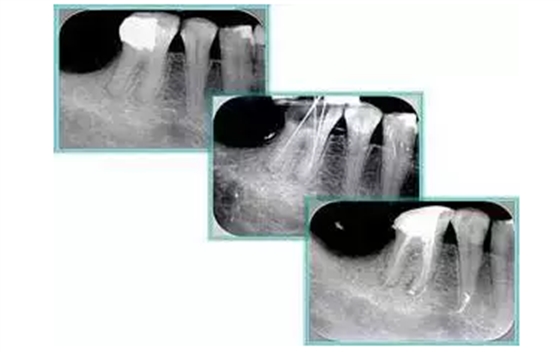

6. 鈣化

常見有修復(fù)性鈣化和增齡性鈣化。下面為根管鈣化 X 線片。

解決方法: ( 1 )清楚根管系統(tǒng)解剖形態(tài)。 ( 2 )安全頭的金剛砂鉆開髓,低速球鉆磨除鈣化牙本( ET20 ,ET40 ,DG-16 )。 ( 3 )徹底去除髓腔周壁的牙本質(zhì)齡。 ( 4 )借助化學(xué)性藥劑,如EDTA 等。

( 5 )初銼選用 8# 或 10#K 銼,平衡力法探察到工作長(zhǎng)度 , H銼上下提拉法使根管擴(kuò)大,提高工作效率

7. 器械折斷

右圖及下圖為器械折斷的 X 線片。箭頭處示折斷器械。

解決方法: ( 1 )取出。 ( 2 )通過。 ( 3 )重新確定工作長(zhǎng)度,充填。 ( 4 )根尖手術(shù)。

器械折斷可以不用取出,取出的原因多是患者心理因素。留在里面的器械關(guān)鍵是進(jìn)行消毒,預(yù)防性使用抗感染藥物,預(yù)防感染。